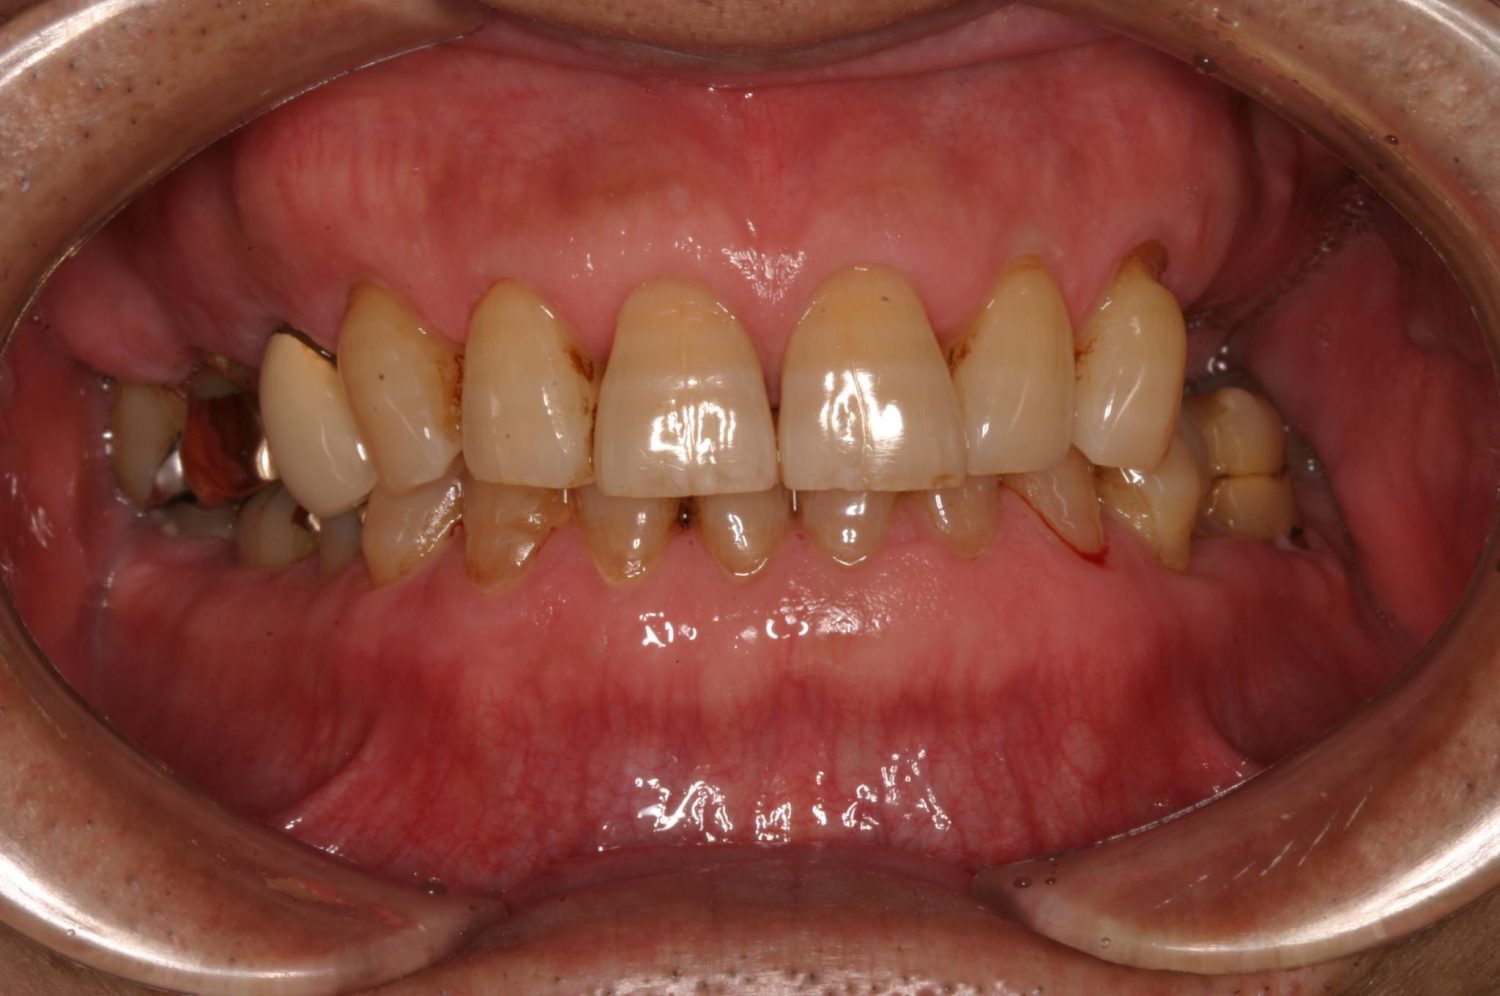

インプラント治療の症例紹介③

Before

After

主訴

むし歯の治療

治療内容

保存不可能な歯の抜歯

下顎にインプラント埋入し咬合再構成

治療費

2,688,400円(税込)

治療期間

14か月

治療回数

21回

想定されたリスク

※上部構造の形態が複雑になるため清掃が難しくなる。インプラント周囲炎の恐れがありました。

多数歯う蝕および多数歯欠損による咬合崩壊、保存不可能な歯の抜歯により上下無歯顎に。下顎に6本インプラント埋入する事で咬合再構成を行った。